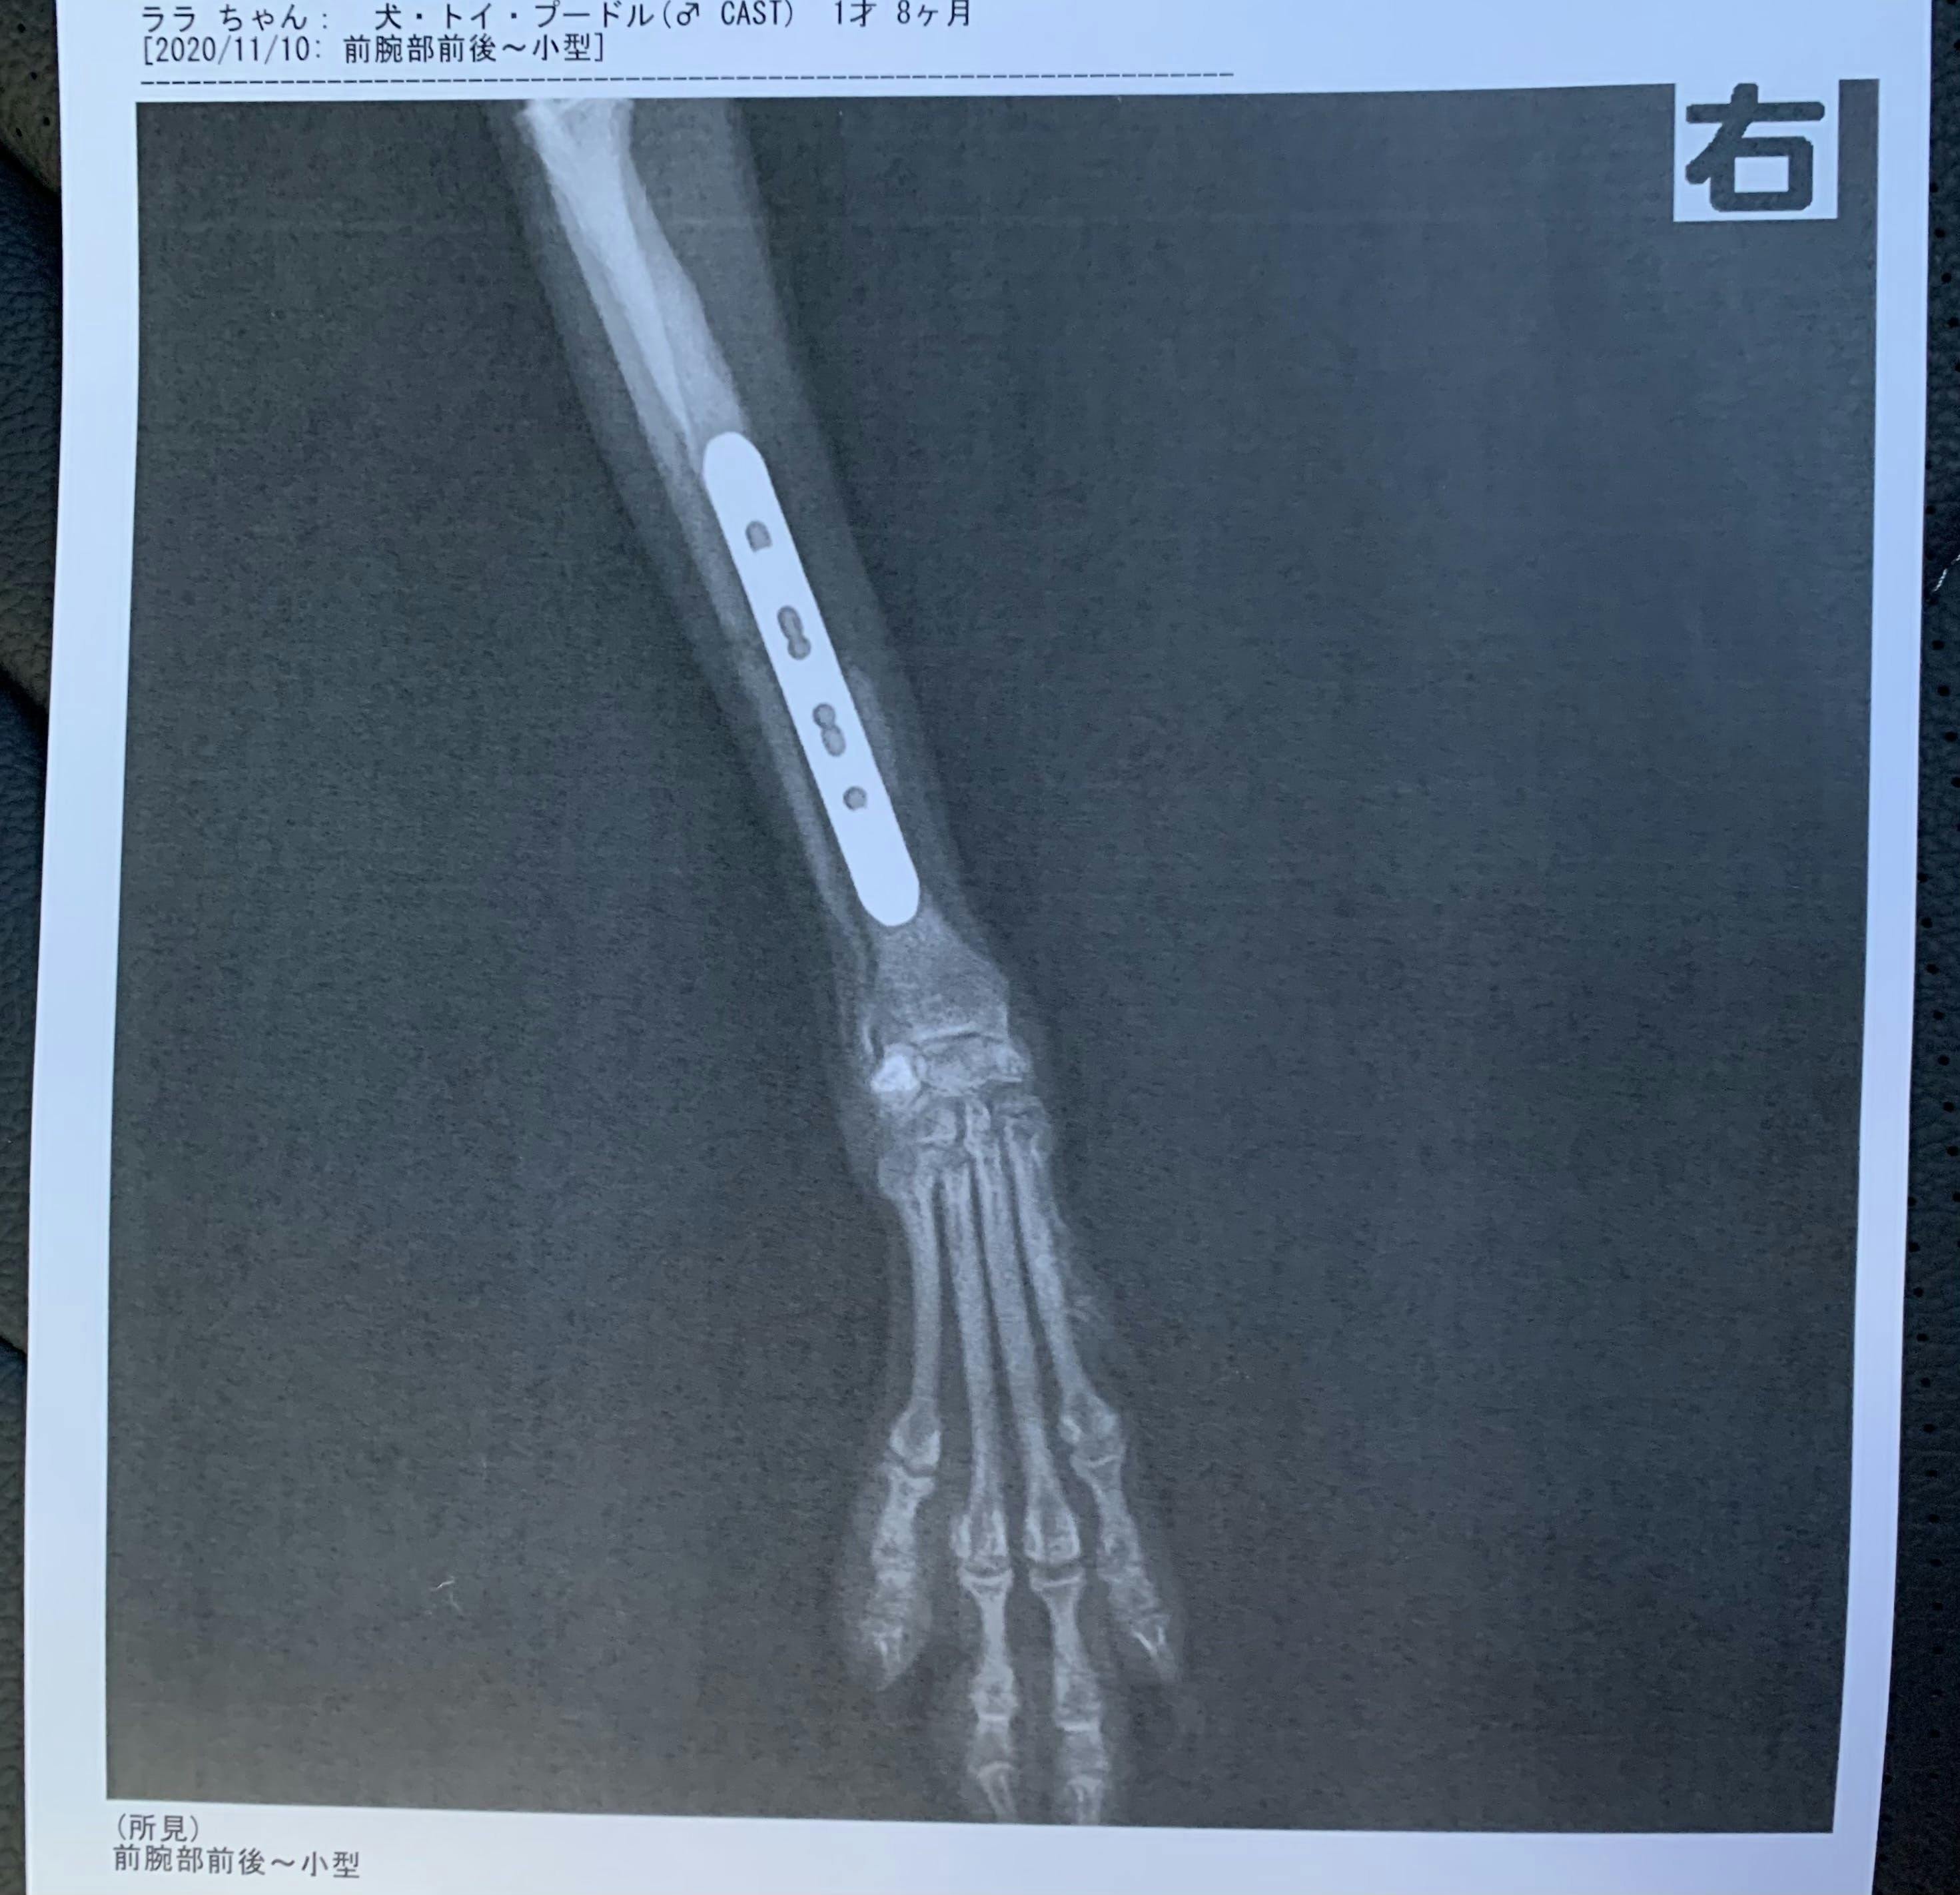

現在愛犬ララは骨折してからボルドを4本入れ入院しています。どうか皆様のご協力いただけませんでしょうか。

現在ボルドを右足に4本入れて固定していて、12月〜来年の1月に骨が治っていれば2つのボルドを取り除く手術をします。状況を見て完治していれば残りの2つのボルドを取り除く手術をします。

実際にボルドでとめている写真です。